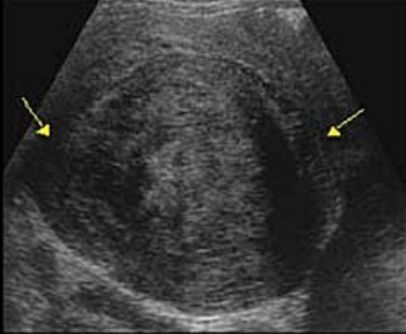

- Her initial ultrasound showed a large subserosa fibroid of 15/15/10cm on the dorsal aspect of the uterus.

- Abdominal ultrasound showed a large subserosa fibroid on the dorsal aspect of the uterus.